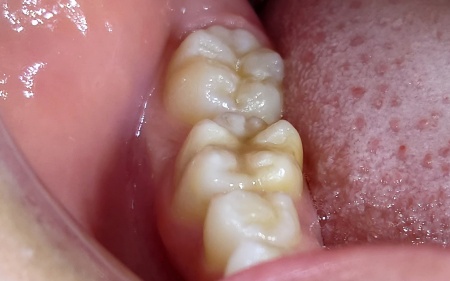

治療後

虫歯の部分をしっかり取り除いたうえで再度コンポジットレジンで修復する方法を提案し、同意いただきました。

この方法であれば保険診療の範囲内で行うことができ、比較的短期間で治療が完了します。加えて、歯の色になじみやすく自然な仕上がりになる点がメリットです。

一方で、奥歯は噛む力が強くかかるため、時間の経過とともにすり減りや劣化が起こる可能性があります。

まず、右下の奥歯2本に入っていた過去の詰め物を丁寧に取り外し、虫歯に感染している部分を確認しながら慎重に除去します。

その後、削った部分に歯の色に合わせたコンポジットレジンを詰め、専用の光を当ててしっかりと硬化させました。

最後に、噛み合わせを確認しながら形を整え、表面を滑らかに磨き上げて治療を終了しました。

治療回数の目安 1回

おおよその費用 保険診療内